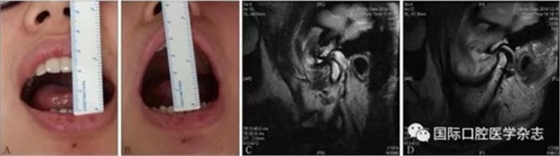

A:術前開口度;B:術后開口度;C:術前影像學檢查片;D:術后影像學檢查片。

圖 18 關節(jié)盤復位錨固術前后對比

(1)顳下頜關節(jié)鏡微創(chuàng)治療。使用關節(jié)鏡治療的適應證:顳下頜關節(jié)紊亂病,保守治療效果不佳,病情較重者(圖17)。2)顳下頜關節(jié)盤復位錨固術(圖18)。使用顳下頜關節(jié)盤復位錨固術治療的適應證:顳下頜關節(jié)紊亂病,保守治療無效,關節(jié)鏡手術效果不佳者。